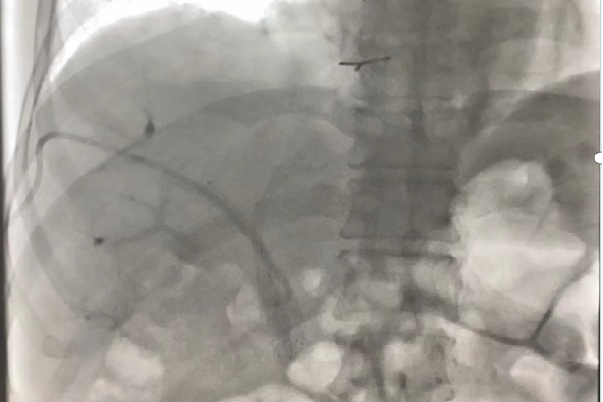

术后4月复查:指标逐渐恢复正常